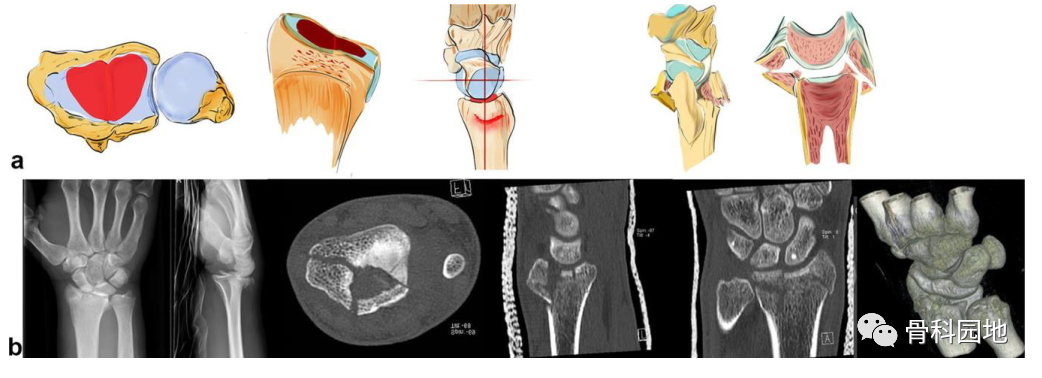

4、中央关键骨块

注:轴向作用力可导致关节面的中央塌陷或背侧和掌侧骨折块的爆裂性骨折(见图b)。这个中央关键骨块与轴或腕骨没有韧带连接。有时,它仅在关节面下略微凹陷,容易被忽视。如果这个中央骨块被更深地撞击到桡骨干中,则附着有稳定韧带的背侧和掌侧皮质骨都会像郁金香一样张开(见图 a)